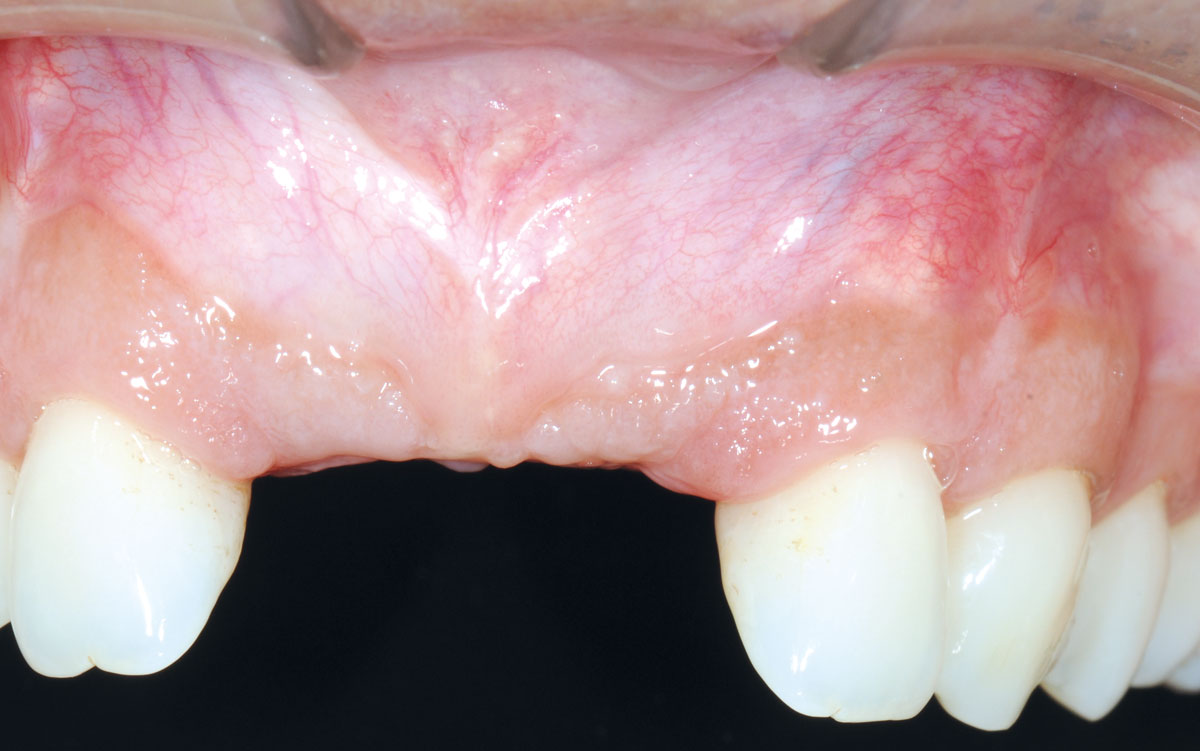

21/26 - 6 months after surgery: healthy soft tissuesBone augmentation in aesthetic zone with maxgraft® bonering - Dr. A. Patel